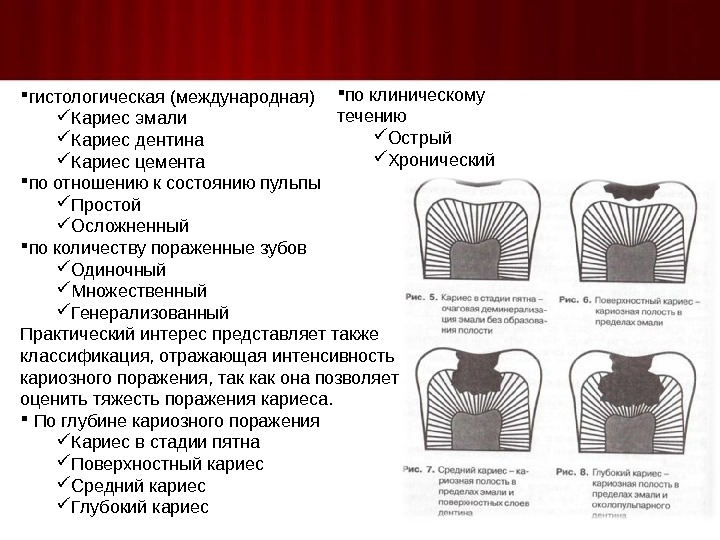

Раздел: Необычные решения